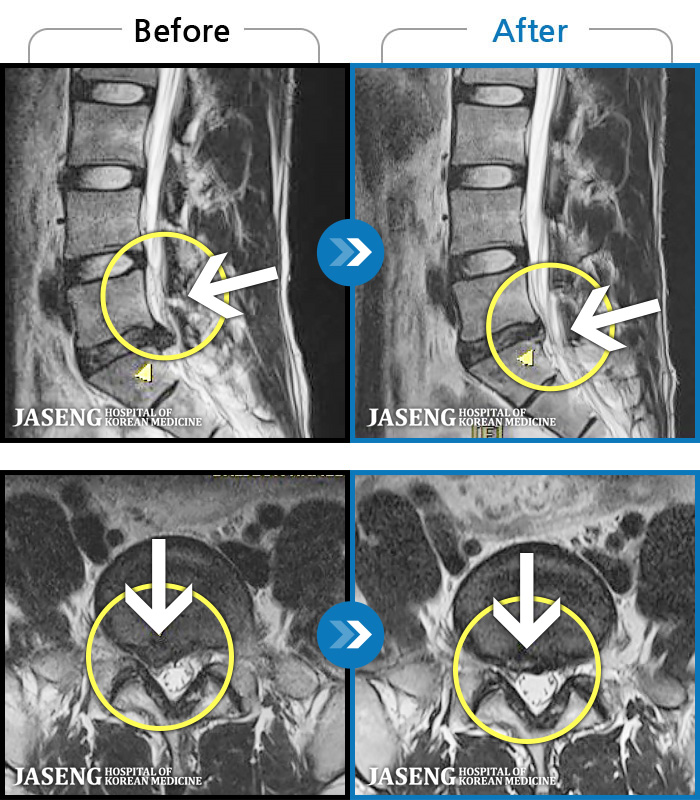

Before

After

양측 허리 통증과 좌측 허벅지까지 동반되는 저림증상 있고, 앉거나 걸을 때 통증 심화되어 내원하셨습니다.

2024.12.11 ~ 2025.11.01